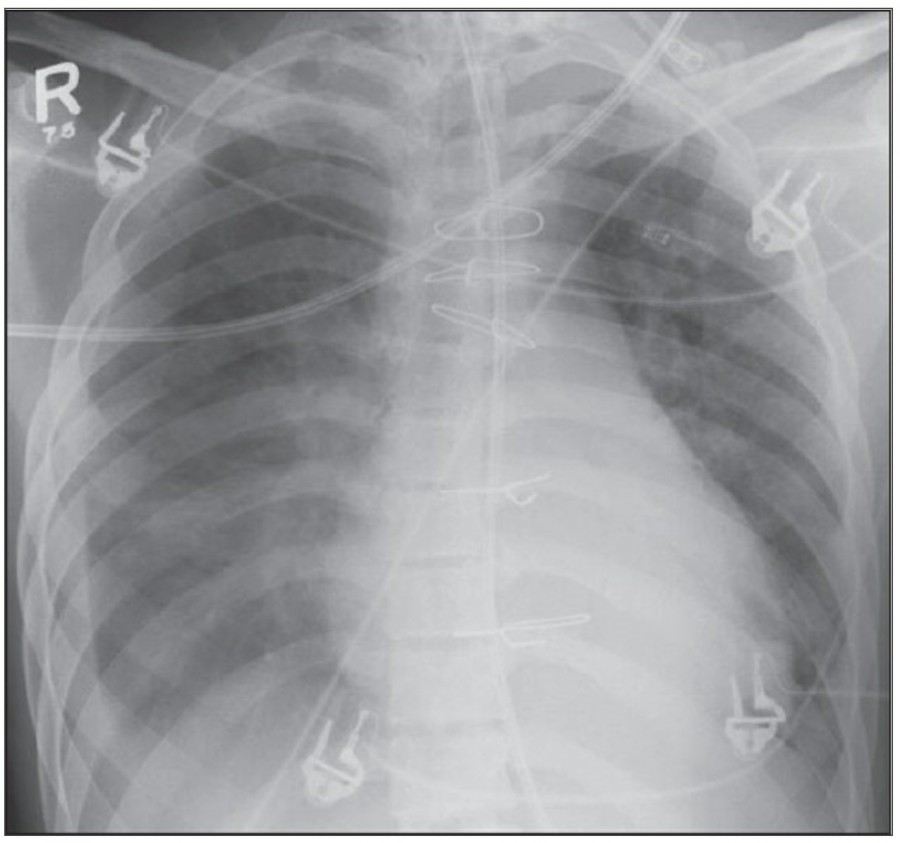

The Normal Chest X-ray중환자실에서 일반적으로 PA chest X ray는 거의 시행하지 않으며, 주로 AP(anteroposterior) chest X ray를 시행한다. AP CXR은 upright position에서 최대 흡기 시 patient-to-x-ray plate가 72inches(182.88cm

Pneumothorax

공기는 nondependent position으로 위치하므로, X ray상에서는 환자 자세에 따라 다르게 나타난다. Erect position에서 공기는 lung의 apicolateral surface에 위치하고 얇고 하얀 pleural line이 나타나며 그 뒤로 lung marking이 보이지 않는다.

하지만 pleural line 뒤로 lung marking이 존재한다고 해서 pneumothorax를 배제할 수 없다. Pneumothorax의 진단은 특히 parenchymal disease가 있을 때 진단하기 힘든데, 이는 compliance의 변화 때문에 collapse가 잘 안 되기 때문이다. Skin fold가 pneumothorax와 비슷하게 보이기도 한다.

중환자에서 pneumothorax의 진단은 종종 supine radiograph에서 내릴 수 있다. Supine position에서 공기는 anteromedial 방향으로 모이게 되는데, apical air collection이 있을 경우 large pneumothorax가 있음을 시사한다. 공기는 lung과 diaphragm 사이의 subpulmonic location에 trap 되어 있을 수도 있다. 공기가 costophrenic sulcus로 anterolateral extension 될 경우, 이 costophrenic sulcus의 radiolucency를 증가시키는데, 이를 deep sulcus sign이라고 한다. Subpulmonic pneumothorax의 다른 특징으로 diaphragm의 superior surface와 IVC 윗부분이 뚜렷하게 보일 수 있다.

중환자에서 tension pneumothorax의 진단은 매우 힘들다. ARDS와 같은 lung의 병리적인 기전이 lung compliance를 감소시킴으로써 total lumg collapse를 막는다. 또한 tension pneumothorax의 특징인 mediastinal shift가 PEEP으로 인해 나타나지 않을 수 있다. Chest X ray 상에서 tension pneumothorax는 hemidiaphragm의 depression이나 heart border, SVC, IVC의 이동으로 나타날 수 있다.